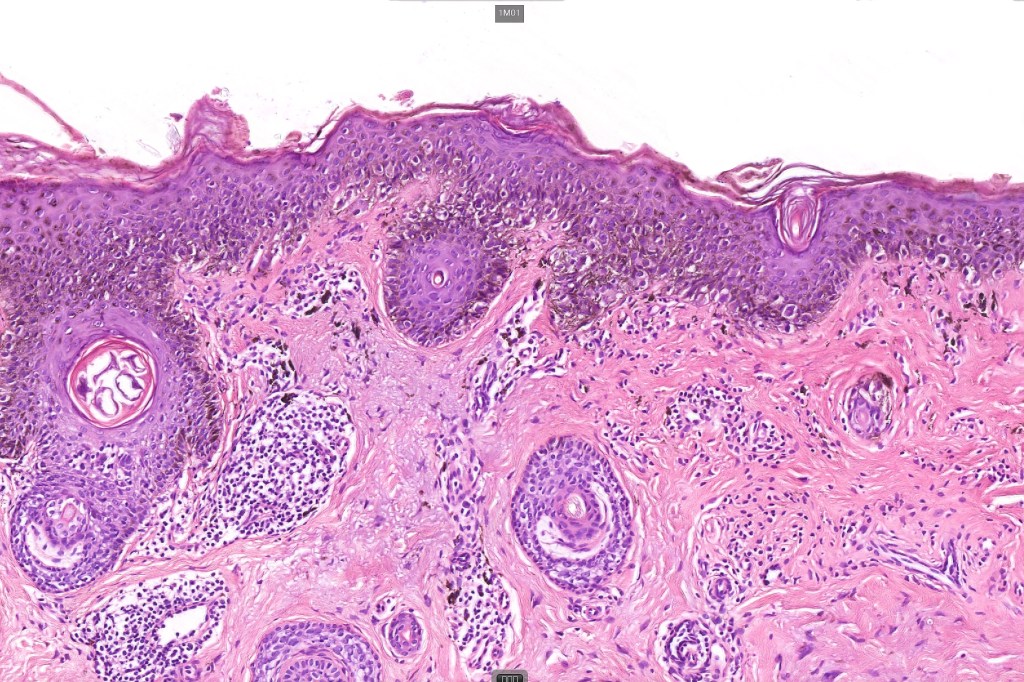

Histological features & immunohistochemstry

•Epidermal atrophy & solar elastosis

•Atypical melanocytes located predominantly along the basal layer of the epidermis, singly, in short arrays or extensively involving the whole epidermis

•Cytoplasmic retraction artifact, nuclear hyperchromatism with irregular borders

•Multinucleate giant cells

•Nest formation present in more advanced cases

•Adnexal involvement

•Dense melanin pigmentation may affect the whole epidermis making it difficult to determine which cells are melanocytes & which are keratinocytes! DAB-lablled antibodies should be avoided as they can be impossible to interpret

•Pagetoid spread

•Dermal melanophages & lymphocytic infiltration